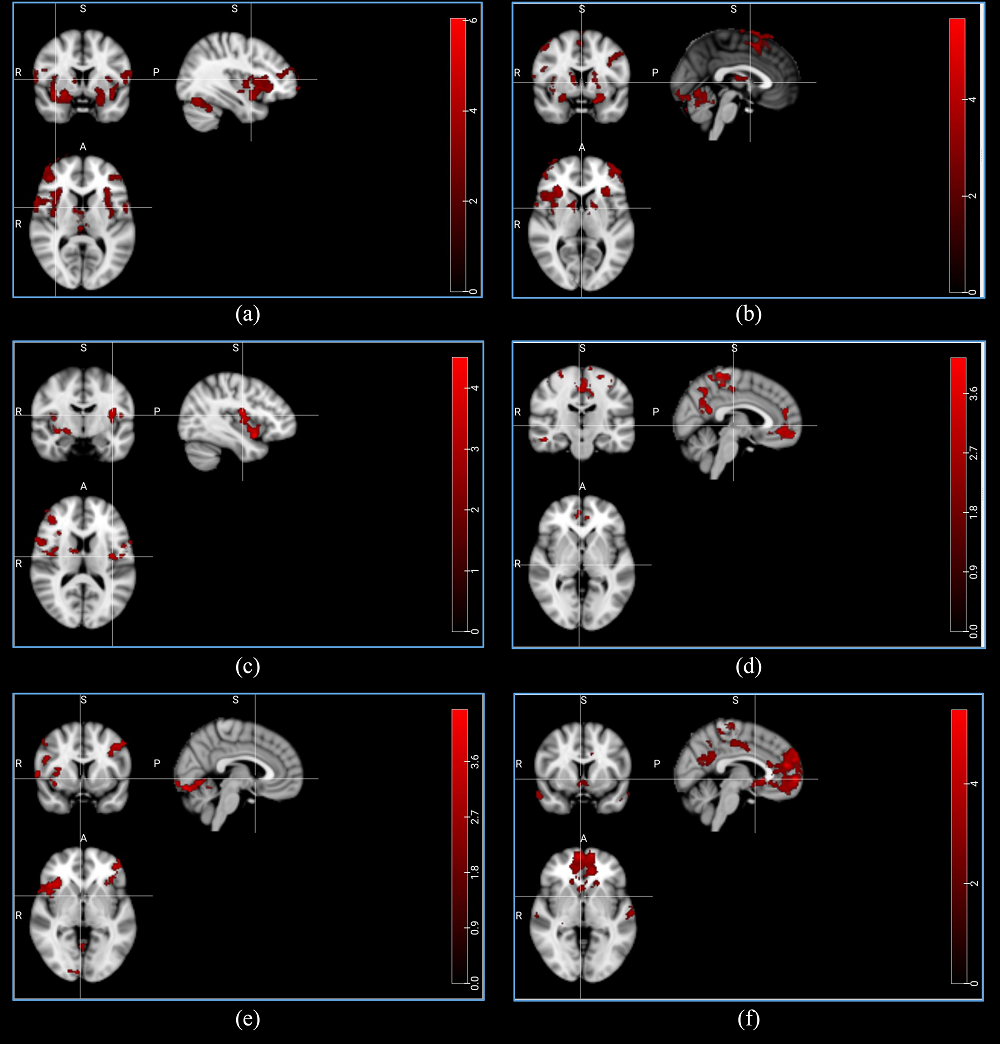

Olfactory system is a vital sensory system in mammals, giving them the ability to connect with their environment. Anosmia, or the complete loss of olfaction ability, which could be caused by injuries, is an interesting topic for inspectors with the aim of diagnosing patients. Sniffing test is currently utilized to examine if an individual is suffering from anosmia; however, functional Magnetic Resonance Imaging (fMRI) provides unique information about the structure and function of the different areas of the human brain, and therefore this noninvasive method could be used as a tool to locate the olfactory-related regions of the brain. In this study, by recruiting 31 healthy and anosmic individuals, we investigated the neural BOLD responses in the olfactory cortices following two odor stimuli, rose and eucalyptus, by using a 3T MR scanner. Comparing the two groups, we observed a network of brain areas being more active in the normal individuals when smelling the odors. In addition, a number of brain areas also showed an activation decline during the odor stimuli, which is hypothesized as a resource allocation deactivation. This study illustrated alterations in the brain activity between the normal individuals and anosmic patients when smelling odors, and could potentially help for a better anosmia diagnosis in the future.